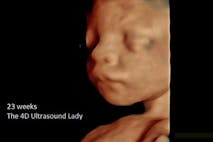

Last month, pro-life leaders and enthusiasts gathered in Providence to celebrate the dedication of a new mobile clinic that will begin offering women throughout Rhode Island free ultrasounds and pregnancy testing. The work of the mobile clinic (named Ancora Women’s Mobile Care Center, and housed in a converted van) is made possible largely through donations from the North American Catholic Educational Programming Foundation, and the Knights of Columbus.

“The van cost close to $150,000 to purchase and outfit for medical use, as well as an additional $50,000 to staff and maintain. Costs include an ultrasound unit, a seating area and couch for the woman receiving services and a nurse sonographer to provide the ultrasounds.”

Susan Baker, a registered nurse who will serve as sonographer of the mobile clinic, stated she is confident the new clinic will save many babies’ lives and will empower the pro-life community to better support women in life-affirming decisions.